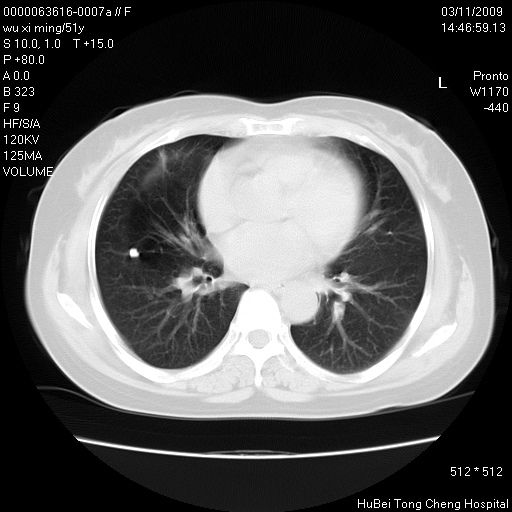

患者 女,51岁。因“胆囊炎,胆囊结石”,行常规术前胸部x线检查发现:右上肺结节病灶,建议行进一步检查。患者无咳嗽、咳痰及咯血等呼吸道症状,近期出现背部疼痛不适。

胸部ct轴位平扫(层厚10mm,螺距1.5,重建间隔10mm;部分层面:层厚3mm,螺距1.0,重建间隔3mm),图像如下:

右肺周围型肺癌伴肺内转移信胸椎转移

支持--右肺周围型肺癌---胸椎转移

右肺周围型肺癌伴肺内转移及胸椎转移。已无手术机会。